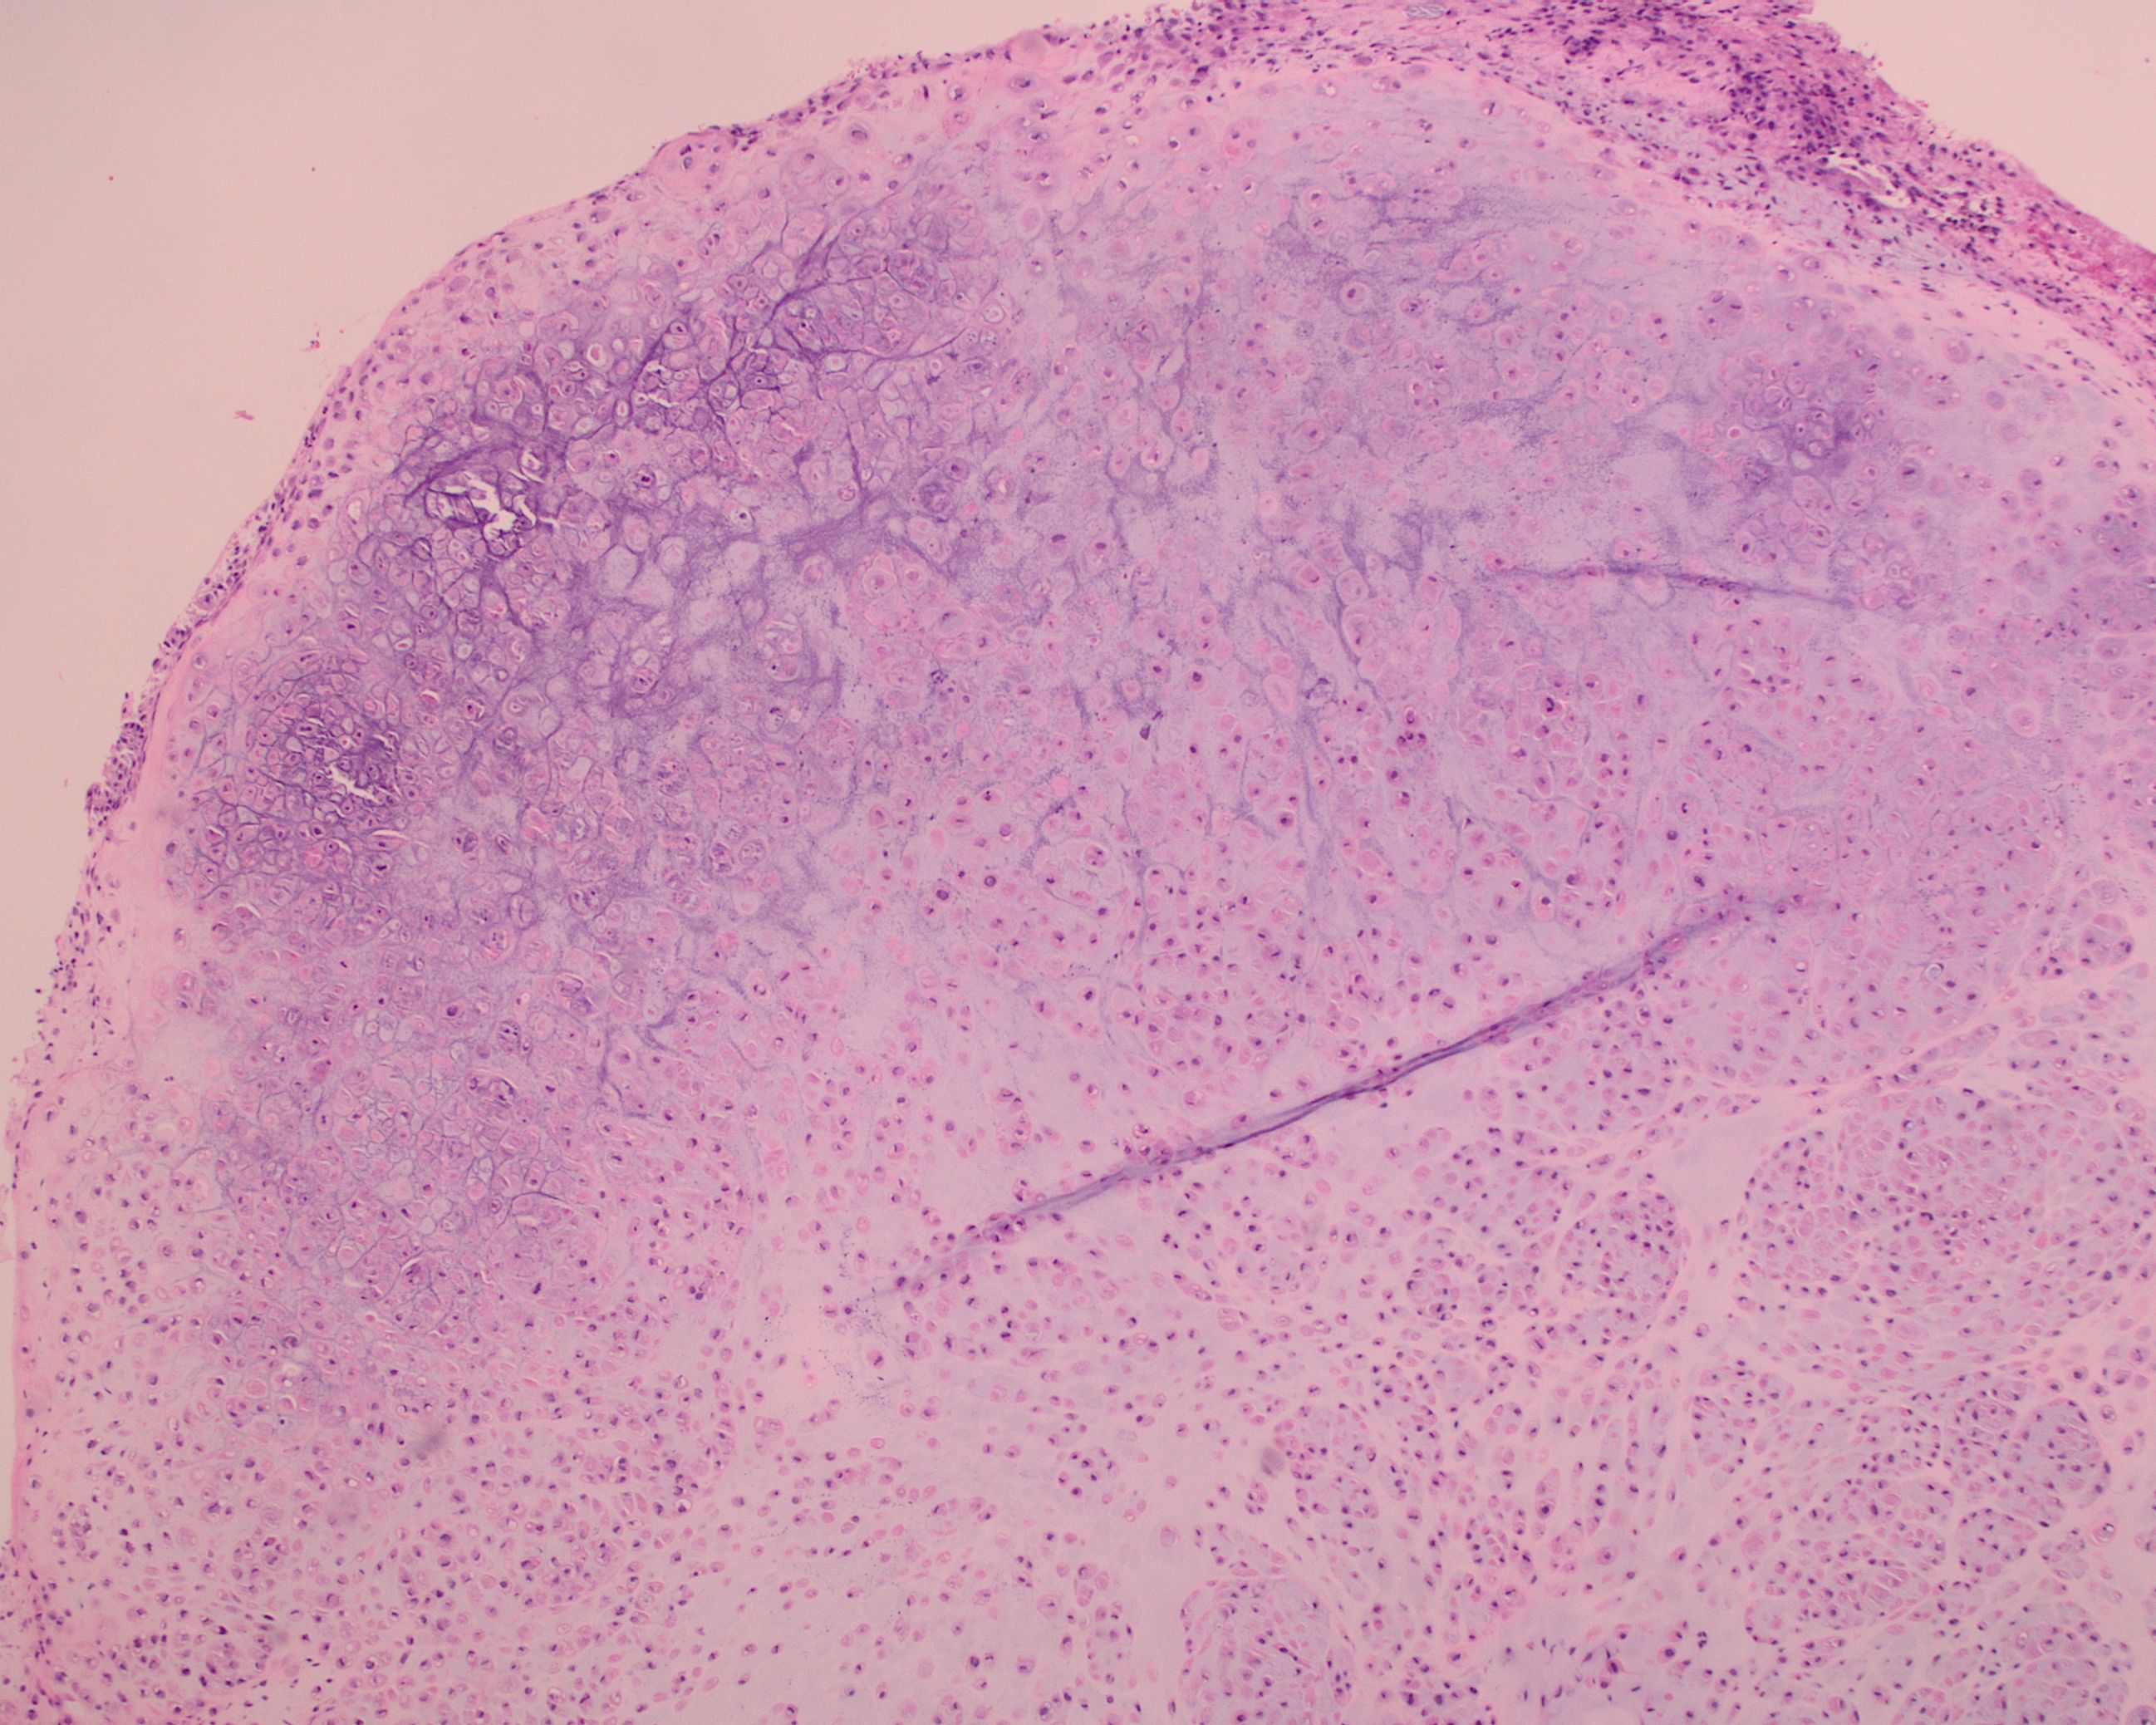

A 55 year-old presents with nodular mass in the temporomandibular joint with erosion of the glenoid fossa. Histologic sections from this lesion are shown below.

This is a newly recognized group of benign soft‑tissue tumors termed calcified chondroid mesenchymal neoplasms (CCMN). These tumors most often arise in the temporomandibular joint and distal extremities, show nodular/lobular growth of polygonal to stellate cells in a chondroid matrix, and frequently contain grungy or lace‑like (chondroblastoma‑like) calcifications, sometimes with CPPD crystal deposition and focal tenosynovial giant cell tumor (TGCT)-like features. Using targeted RNA sequencing, these tumors harbor recurrent FN1-receptor tyrosine kinase gene fusions in most cases, most commonly FN1::FGFR2, but also FN1::FGFR1 and novel fusions involving MERTK, NTRK1, and TEK, supporting a shared molecular pathogenesis. Although these lesions overlap morphologically with chondroblastoma‑like soft tissue chondroma, chondroid TGCT, and tumoral pseudogout, their distinctive fusion profile and expanded morphologic spectrum justify recognition as a separate diagnostic category with generally indolent behavior after excision.